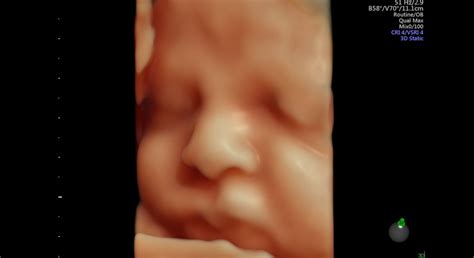

V tomto období sa znižuje riziko potratu a príznaky tehotenstva u matky často ustúpia. Plod rastie a vyvíja sa ďalej, formujú sa vonkajšie pohlavné orgány, kosti tvrdnú a začínajú sa objavovať prvé pohyby. Medzi 16. až 24. týždňom tehotenstva by mala žena ucítiť prvé pohyby bábätka. V tomto trimestri sa vykonáva morfologický ultrazvuk na detailné posúdenie vývoja plodu.